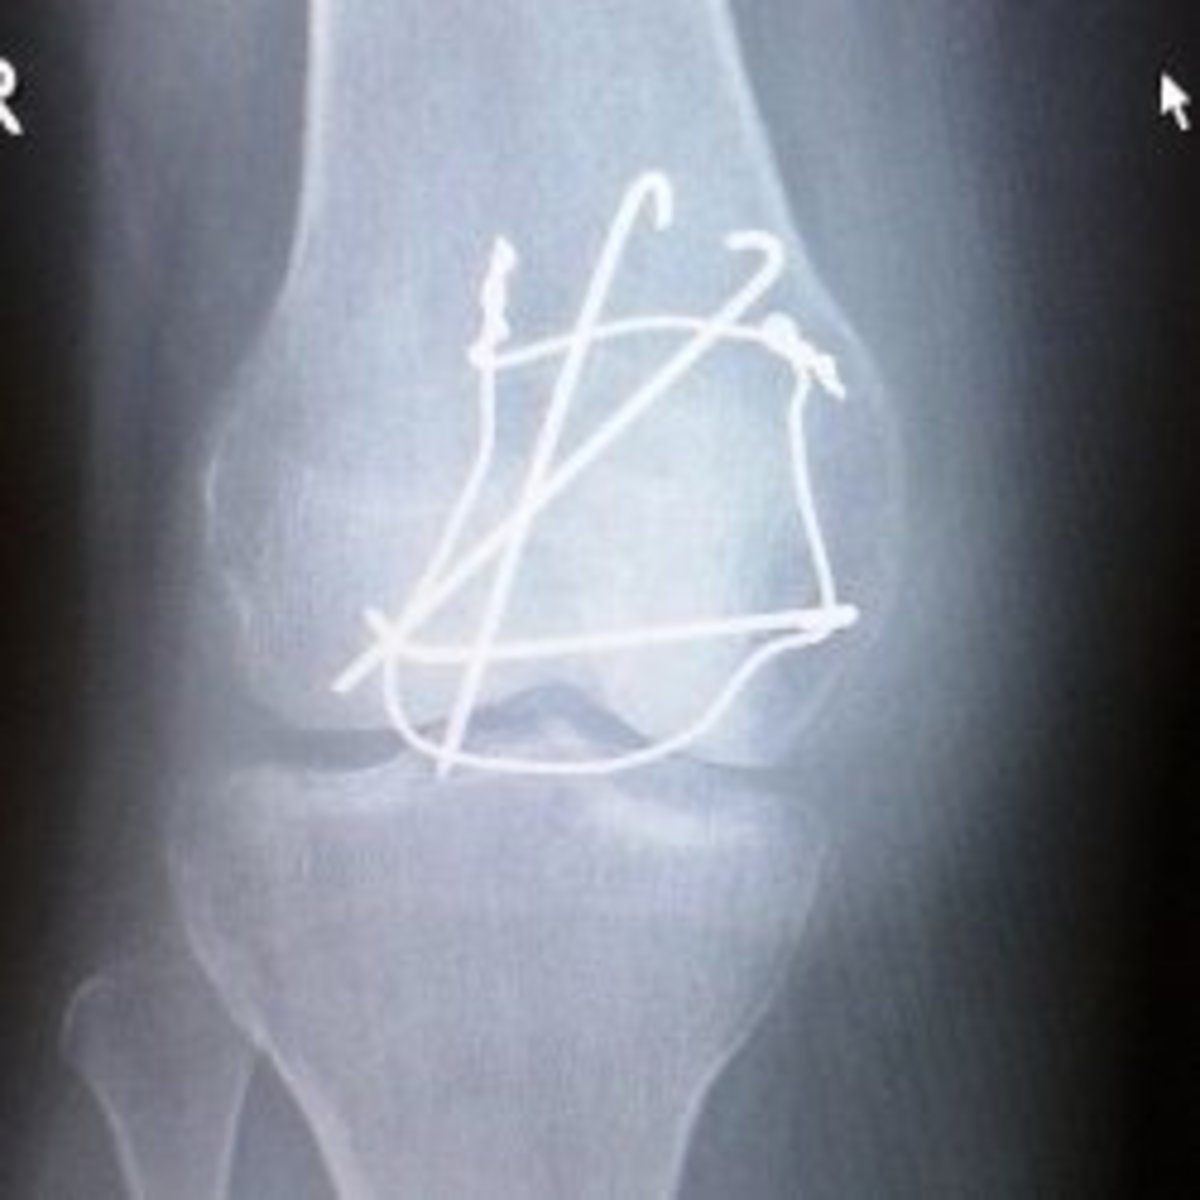

From uwmsk.org

UW MSK Resident Projects Intraarticular Bodies How To Relocate Knee A helmet hitting the knee) or from a sudden twist or pivoting of the leg (e.g. As long as the diagnosis is clear, a knowledgeable healthcare provider will manually relocate the kneecap as soon as. A ballet dancer landing poorly). There are a few main symptoms of a dislocated kneecap that most. Patellar dislocation is usually caused by either a. How To Relocate Knee.